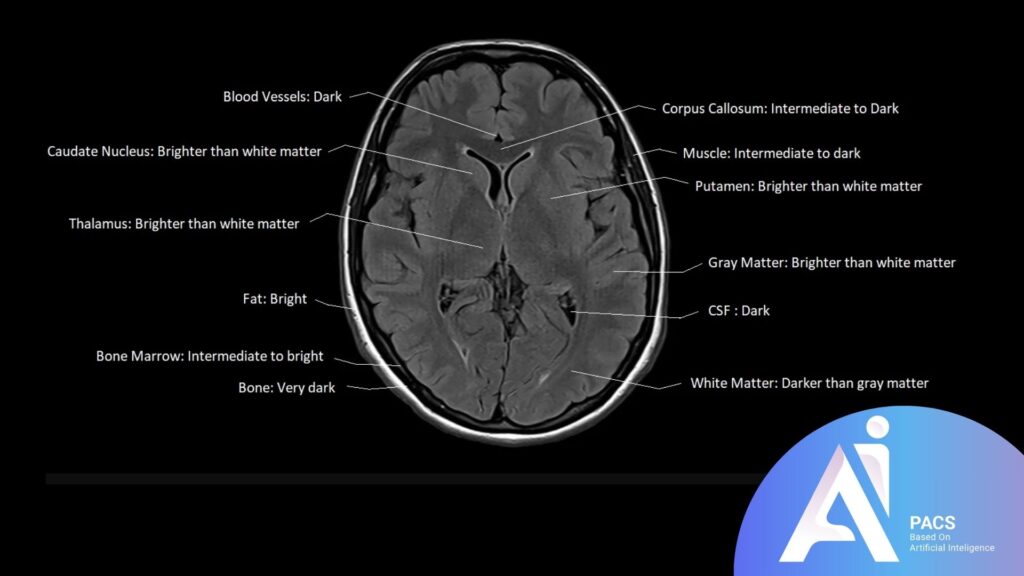

Comparison to other MRI sequences for context

Compared to standard T1 and T2 MRI sequences, FLAIR provides a unique advantage in brain imaging by isolating abnormalities near or within fluid-filled spaces. While T2-weighted imaging also highlights areas of high water content, the bright CSF can obscure details, especially near the brain’s ventricles. In contrast, FLAIR’s fluid suppression reveals subtle brain lesions, making it a crucial tool for diagnosing conditions like multiple sclerosis, stroke, and infections that might be harder to detect with other sequences.